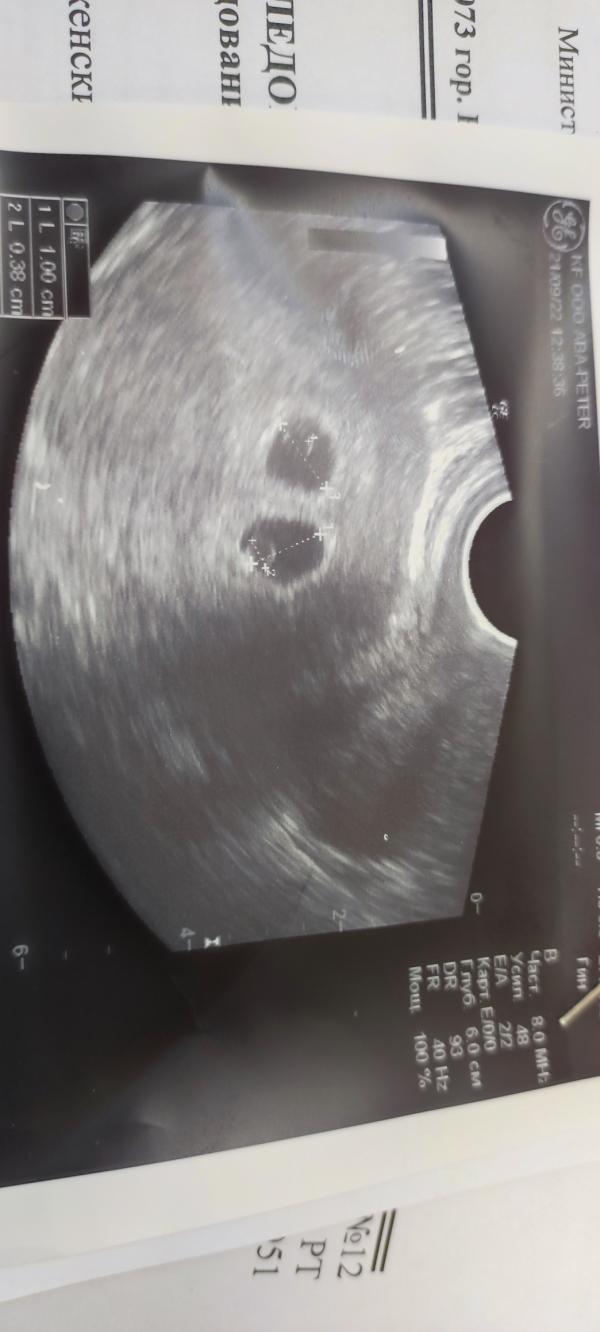

Девочки всем привет, ну вот и наше первое узи🙏🥰у нас будет двойня🙏🤰одновременно переполняет радость и страх, сможем ли мы поднять двоих 🙏😌